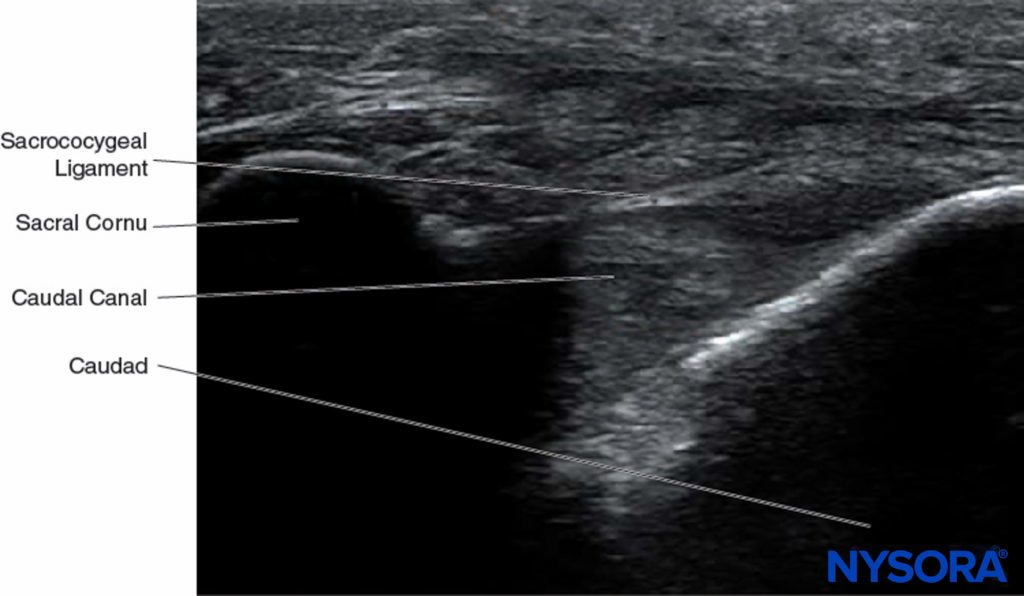

With the patient in the prone position, the sacral cornua are identified by palpation using the technique described in the section on anatomic landmarks. Sterile skin preparation and draping of the entire region are performed. A low-frequency curvilinear probe is placed in the transverse plane across the two sacral cornua (Figure 10). The sacral cornua can be visualized as two symmetric hyperechoic arches, with a hypoechoic shade underneath both lines, bridging these two structures. Traversing this hypoechoic area are two hyperechoic lines, the superficial one being the sacrococcygeal ligament and the deeper one line being the dorsal bony surface of the sacrum (Figure 11). A 22-gauge needle is inserted into the space between the two cornua. A distinct “pop” is felt as the needle tip penetrates the sacrococcygeal ligament.

FIGURE 11. Ultrasound image along the short axis of the caudal canal, depicting the sacral cornua, sacrococcygeal ligament, and the caudal canal.

At this point, the orientation of the probe is changed into the sagittal plane (Figure 12), and the caudal canal is identified as a hypoechoic canal tapering off caudally and bordered by dorsal and ventral hyperechoic bands. The dorsal band is formed by the dorsal bony aspect of the caudal canal cranially and the sacrococcygeal ligament caudally. The ventral band is formed by the ventral bony surface of the caudal canal (Figure 13).

FIGURE 13. Ultrasonographic image along the long axis of the caudal canal depicting the long-axis view of the caudal canal.